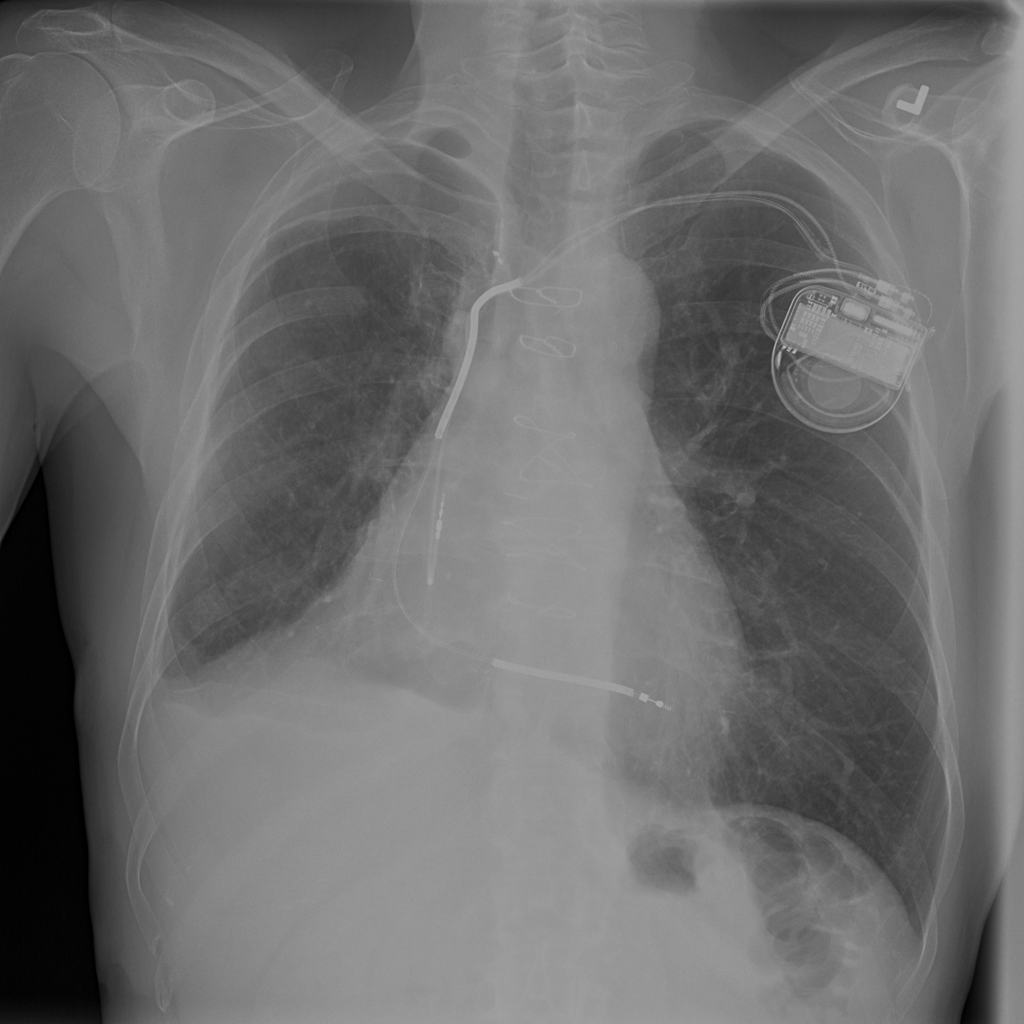

PAT-4639 · IMG-021Effusion

PAT-4639 · IMG-021

PA